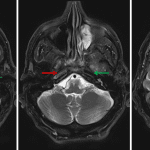

- Possible restricted diffusion in the posterior intraorbital right optic nerve

- Asymmetric small caliber of the left optic nerve with associated T2/FLAIR signal hyperintensity

- Abnormal flow-related signal in the visualized portions of the right internal carotid artery, though there is normal flow-related signal loss in the right MCA and ACA

- Internal carotid artery occlusion

Abnormal flow-related signal in the visualized portions of the right internal carotid artery, raising concern for high grade stenosis or occlusion. Recommend head and neck CTA for further evaluation.

Possible restricted diffusion in the posterior intraorbital right optic nerve, concerning for ischemic optic neuropathy. Recommend ophthalmology evaluation.

Asymmetric small caliber of the left optic nerve with associated T2/FLAIR signal hyperintensity, suggestive of sequela of prior optic neuritis.